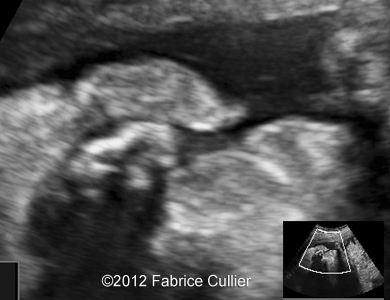

Image 5: At 25 weeks, a cleft palate was suspected also.

3A

3B